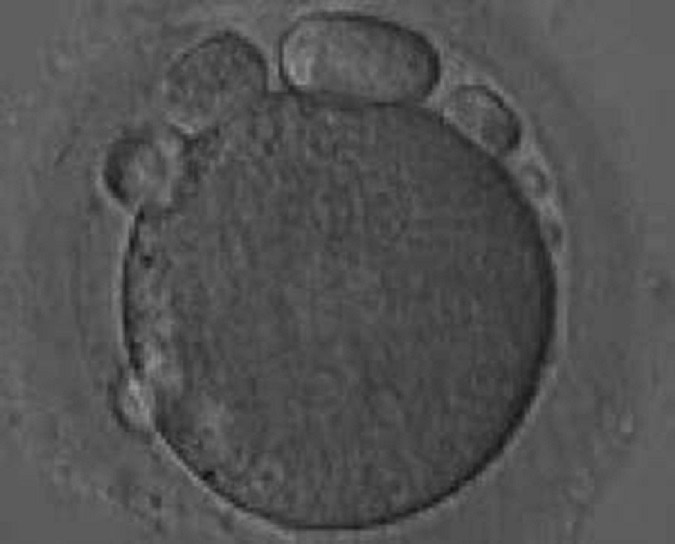

765. На рисунке представлен ооцит